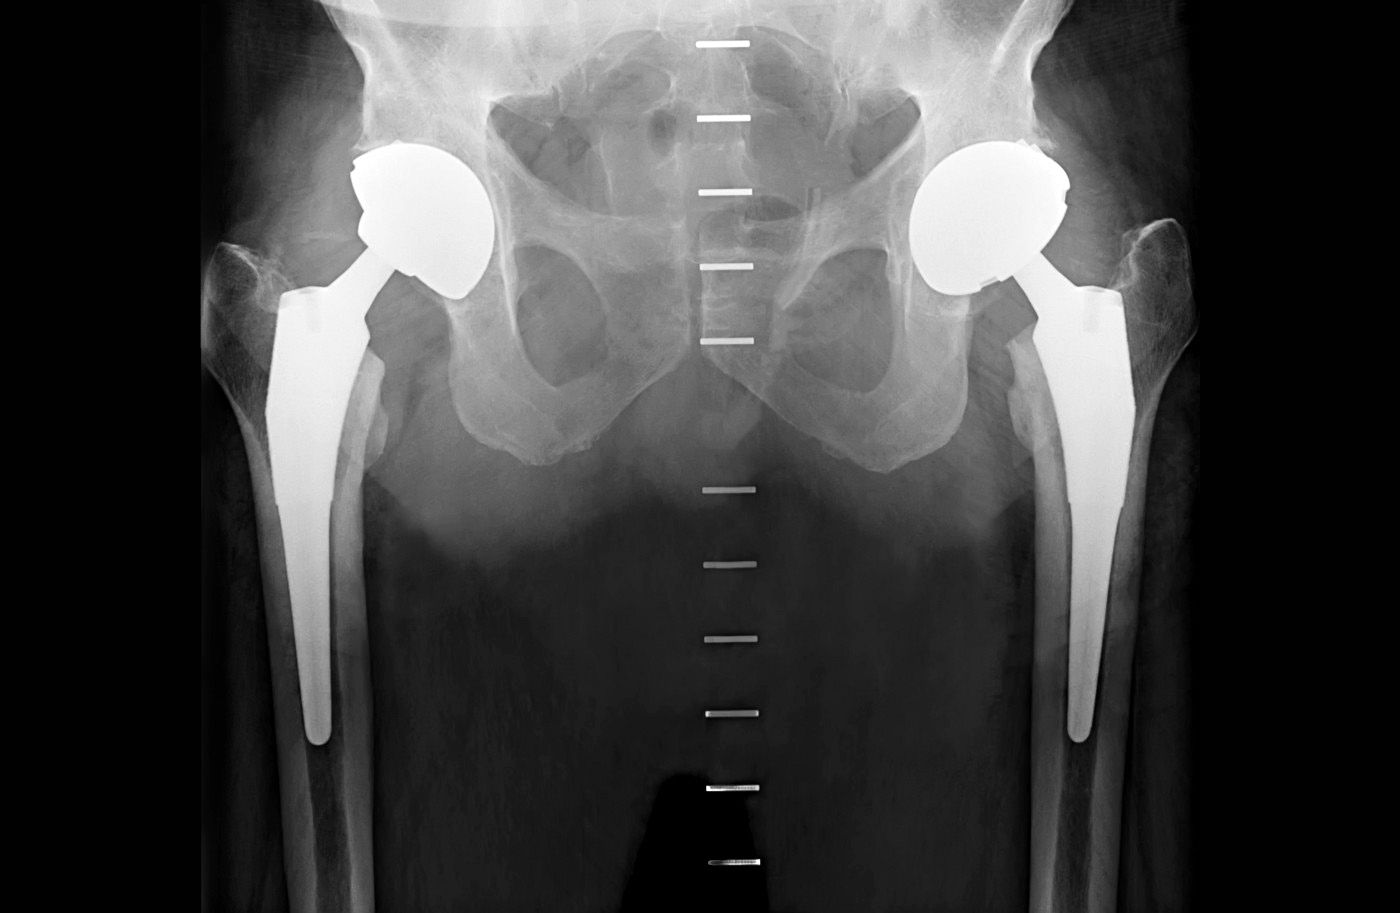

Ron's Story My Double Hip Replacement Hip Replacement Experiences After searching for the right doctor (more on that below), i opted for an anterior hip replacement, rather than a traditional posterior replacement. A patient with ankylosing spondylitis shares his experience of having a total hip replacement surgery at 70 by dr mizan marican, an orthopaedic surgeon. It was all very difficult. Learn about the factors that affect hip replacement. Hip Replacement Experiences.